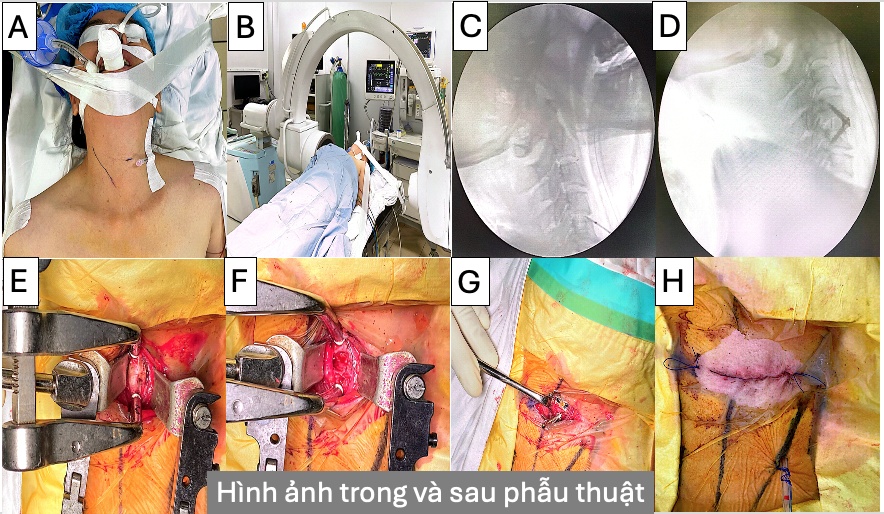

Bệnh nhân được chỉ định phẫu thuật lấy nhân đệm và cố định cột sống cổ qua lối trước (ACDF – Anterior Cervical Discectomy and Fusion).

Sau phẫu thuật, bệnh nhân giảm đau rõ rệt, hết tê tay và vận động bình thường sau 2 tuần. Hiện tại, bệnh nhân được tái khám định kỳ và phục hồi chức năng tích cực.

Kết quả: Ca mổ thành công, minh chứng cho việc phát hiện sớm và điều trị đúng hướng giúp phục hồi hoàn toàn chức năng thần kinh.

Hình 3. Hình ảnh trong (A,B,C,E,F,G,H) và sau mổ (D) theo quy trình phẫu thuật ACDF với sự hỗ trợ của C-arm trong mổ, giúp xác định chính xác vị trí phẫu thuật với đường rạch da 3cm